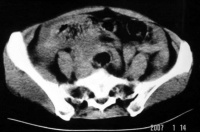

3.CT表现:

(1)输卵管积液或输卵管卵巢囊肿在大多数病例中不能与其他囊性肿块鉴别。

(2)输卵管-卵巢脓肿直径需>2cm以上CT才易于显示,表现为混杂密度肿块,边缘光滑或有毛刺,壁厚而不规则,脓肿壁在增强后比一般囊肿有更明显的强化。当囊内有气体存在时,对诊断脓肿有帮助。

(3)积液时CT值为0~15HU,积脓时CT值为15~40HU。